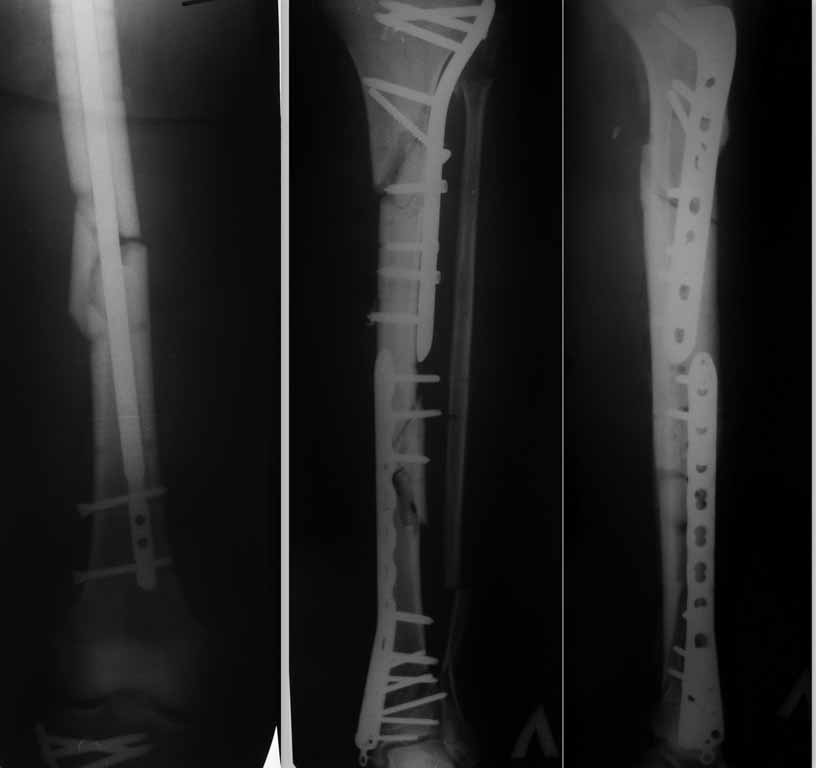

Спасибо большое за комментарии. Я рад что форум быстро откликнулся на сообщение. Дело в том,

что больной уже прооперирован 29.11.11. очень экстравагантным способом в нашей клинике.

оперировал "гуру" поэтому я от комментариев воздержусь. Выкладываю рентгенограммы на ваш

суд.